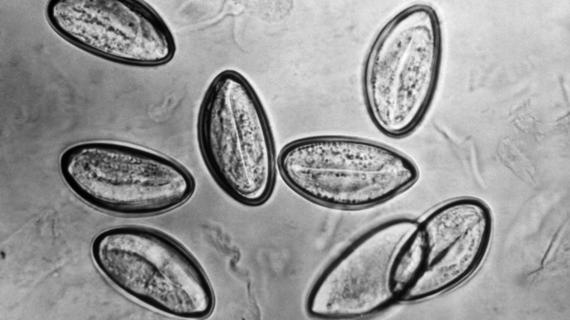

Энтеробиоз – распространенное паразитарное заболевание, которым чаще всего болеют дети в возрасте 4-10 лет. Болезни подвержены и взрослые, но в...

Анализ на энтеробиоз является самым распространенным видом лабораторного исследования. Сдавать его необходимо для получения справки в бассейн, медицинской книжки при устройстве на работу и...